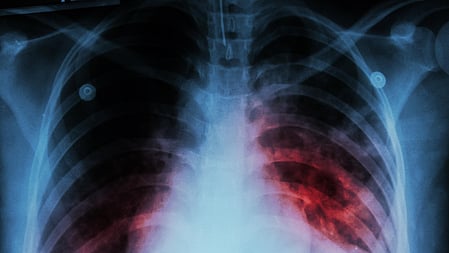

Image used for representational purpose. Photo | IANS

BHUBANESWAR: More than 40 per cent of the population in India carry the tuberculosis bacteria though their microbiological test reports are found to be negative, said an expert on the disease.

Speaking at a programme organised to observe the World TB Week at the Institute of Medical Sciences (IMS) and SUM Hospital, professor at Sri Jagannath Medical College Hospital in Puri, Dr Sudarsan Pothal said although people carry the bacteria, the disease does not get manifested in them and only around 10 per cent of them develop the disease subsequently.

“However, these asymptomatic TB cases keep spreading the disease. The need is to screen all patients coming to a doctor or hospital for treatment of any disease to detect latent tuberculosis in them. This can be done by using portable X-ray machines. The silent carriers will continue to grow and spread the disease unless transmission is stopped through screening,” he said.